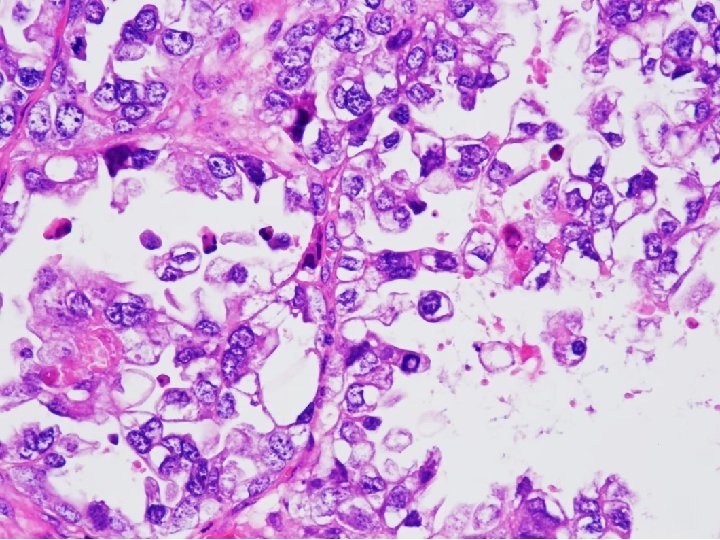

Tissue from uterine cervix, biopsy; Poorly differentiated adenocarcinoma with 1) sheets and papillary features 2) tubulocystic pattern 3) frequent clear cell feature c/w CLEAR CELL CARCINOMA

• Clear cell carcinomas present marked cellular and nuclear pleomorphism; they often have bizarre nuclei and abundant, pale cytoplasm Color Atlas of DDx in Exfoliative and Aspiration Cytopathology, Kini

CYTOPATHOLOGIC FEATURES OF CLEAR CELL CARCINOMA • Arrangement – Cells are isolated, in loosely cohesive groups and in syncytial tissue fragments; hobnail pattern may be present • Cells – Medium to large with poorly defined cell borders; moderate to high N/C ratios; round, polygonal to hobnail type • Nuclei – Large, round, often eccentric, very pleomorphic; coarsely granular to smudgy chromatin; nucleoli are inconsistent; multinucleation • Cytoplasm – Variable, scant to abundant, clear to pale, weakly staining either eosinophilic or cyanophilic • Background – Clean, bloody or inflammatory; naked nuclei Color Atlas of DDx in Exfoliative and Aspiration Cytopathology, Kini